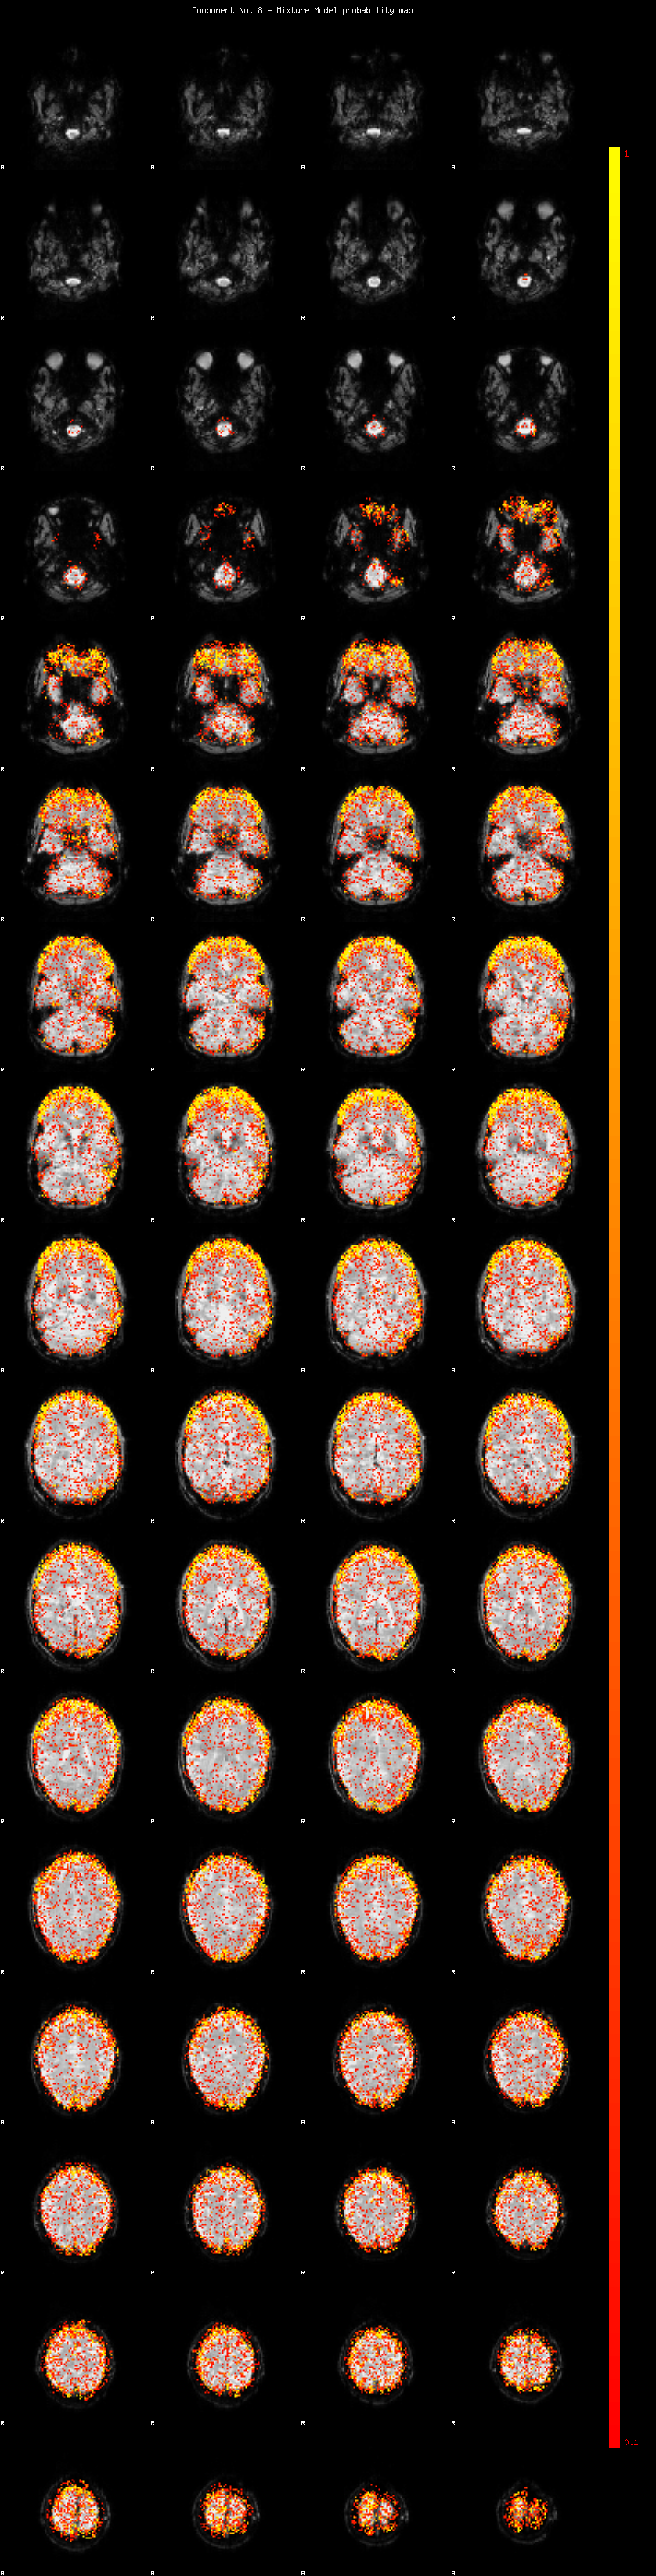

IC_8 Mixture Model fit

Means : -0.000000 3.330625 -2.902231

Vars : 1.000000 5.068361 3.431307

Prop. : 0.840049 0.091129 0.068822